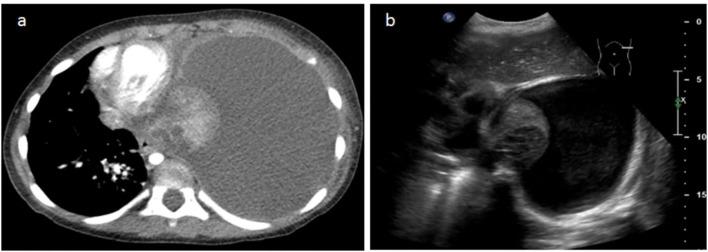

儿童坏死性肺炎:胸部计算机断层扫描与肺部超声检查的对比

The utilization of contrast-enhanced computed tomography (CT) of the chest for the diagnosis of necrotizing pneumonia (NP), a complication of community-acquired pneumonia, is controversial because of the inherent ionizing radiation involved. Over the past few years, the growing availability of bedside Lung Ultrasound (LUS) devices has led to increased use of this nonionizing imaging method for diagnosing thoracic pathology, including pneumonia.

OBJECTIVE

The objectives of this study were as follows: first, to compare the performance of LUS vs. CT in the identification of certain radiological signs of NP, and second, to determine whether LUS could replace CT in the diagnosis of NP.

Pleural effusions were demonstrated almost systematically (100% on CT vs. 95.8% on LUS). Visualization of septations in pleural effusions was clearly superior on LUS (20.4% on CT vs 62.5% on LUS). Concerning the detection of necrosis, we observed a strong correlation between LUS and the gold-standard CT (95.8% on LUS vs. 93.7% on CT). Parenchymal cavities were more easily detected on CT than on LUS (79.1 vs. 35.4%).

CONCLUSION

LUS has shown to be as effective as CT in the diagnosis of NP. The use of CT in patients with NP could be limited to the detection of complications such as bronchopleural fistulae in unfavorably evolving diseases.